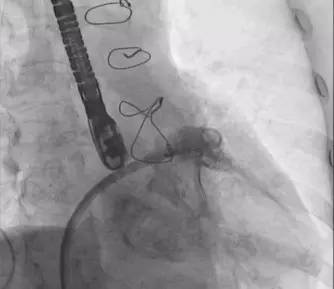

行左心耳封堵术,术前左房肺静脉CTA三维重建如(图1),术中左心耳造影并测量如(图2)(图3),封堵器释放后3D经食道超声心动图(TEE)如(图4)。术后当晚复查超声心动图后,开始应用低分子肝素+华法林,INR达标后,改为华法林+阿司匹林100 mg/d,嘱患者INR控制在1.8~2.5之间。出院1周后患者再次出现咯血,当时测INR 2.0,停用华法林。

图1

图2

图3